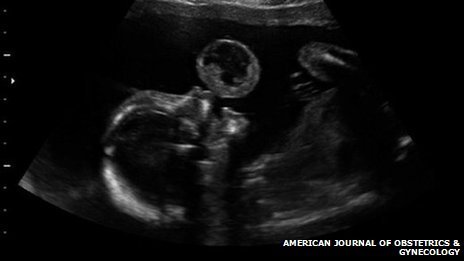

After a scan at 17 weeks, mother Tammy Gonzalez said she “could see a bubble” coming out of her baby’s mouth.

Doctors said it was a very rare tumor called an oral teratoma and there was little chance her daughter would survive.